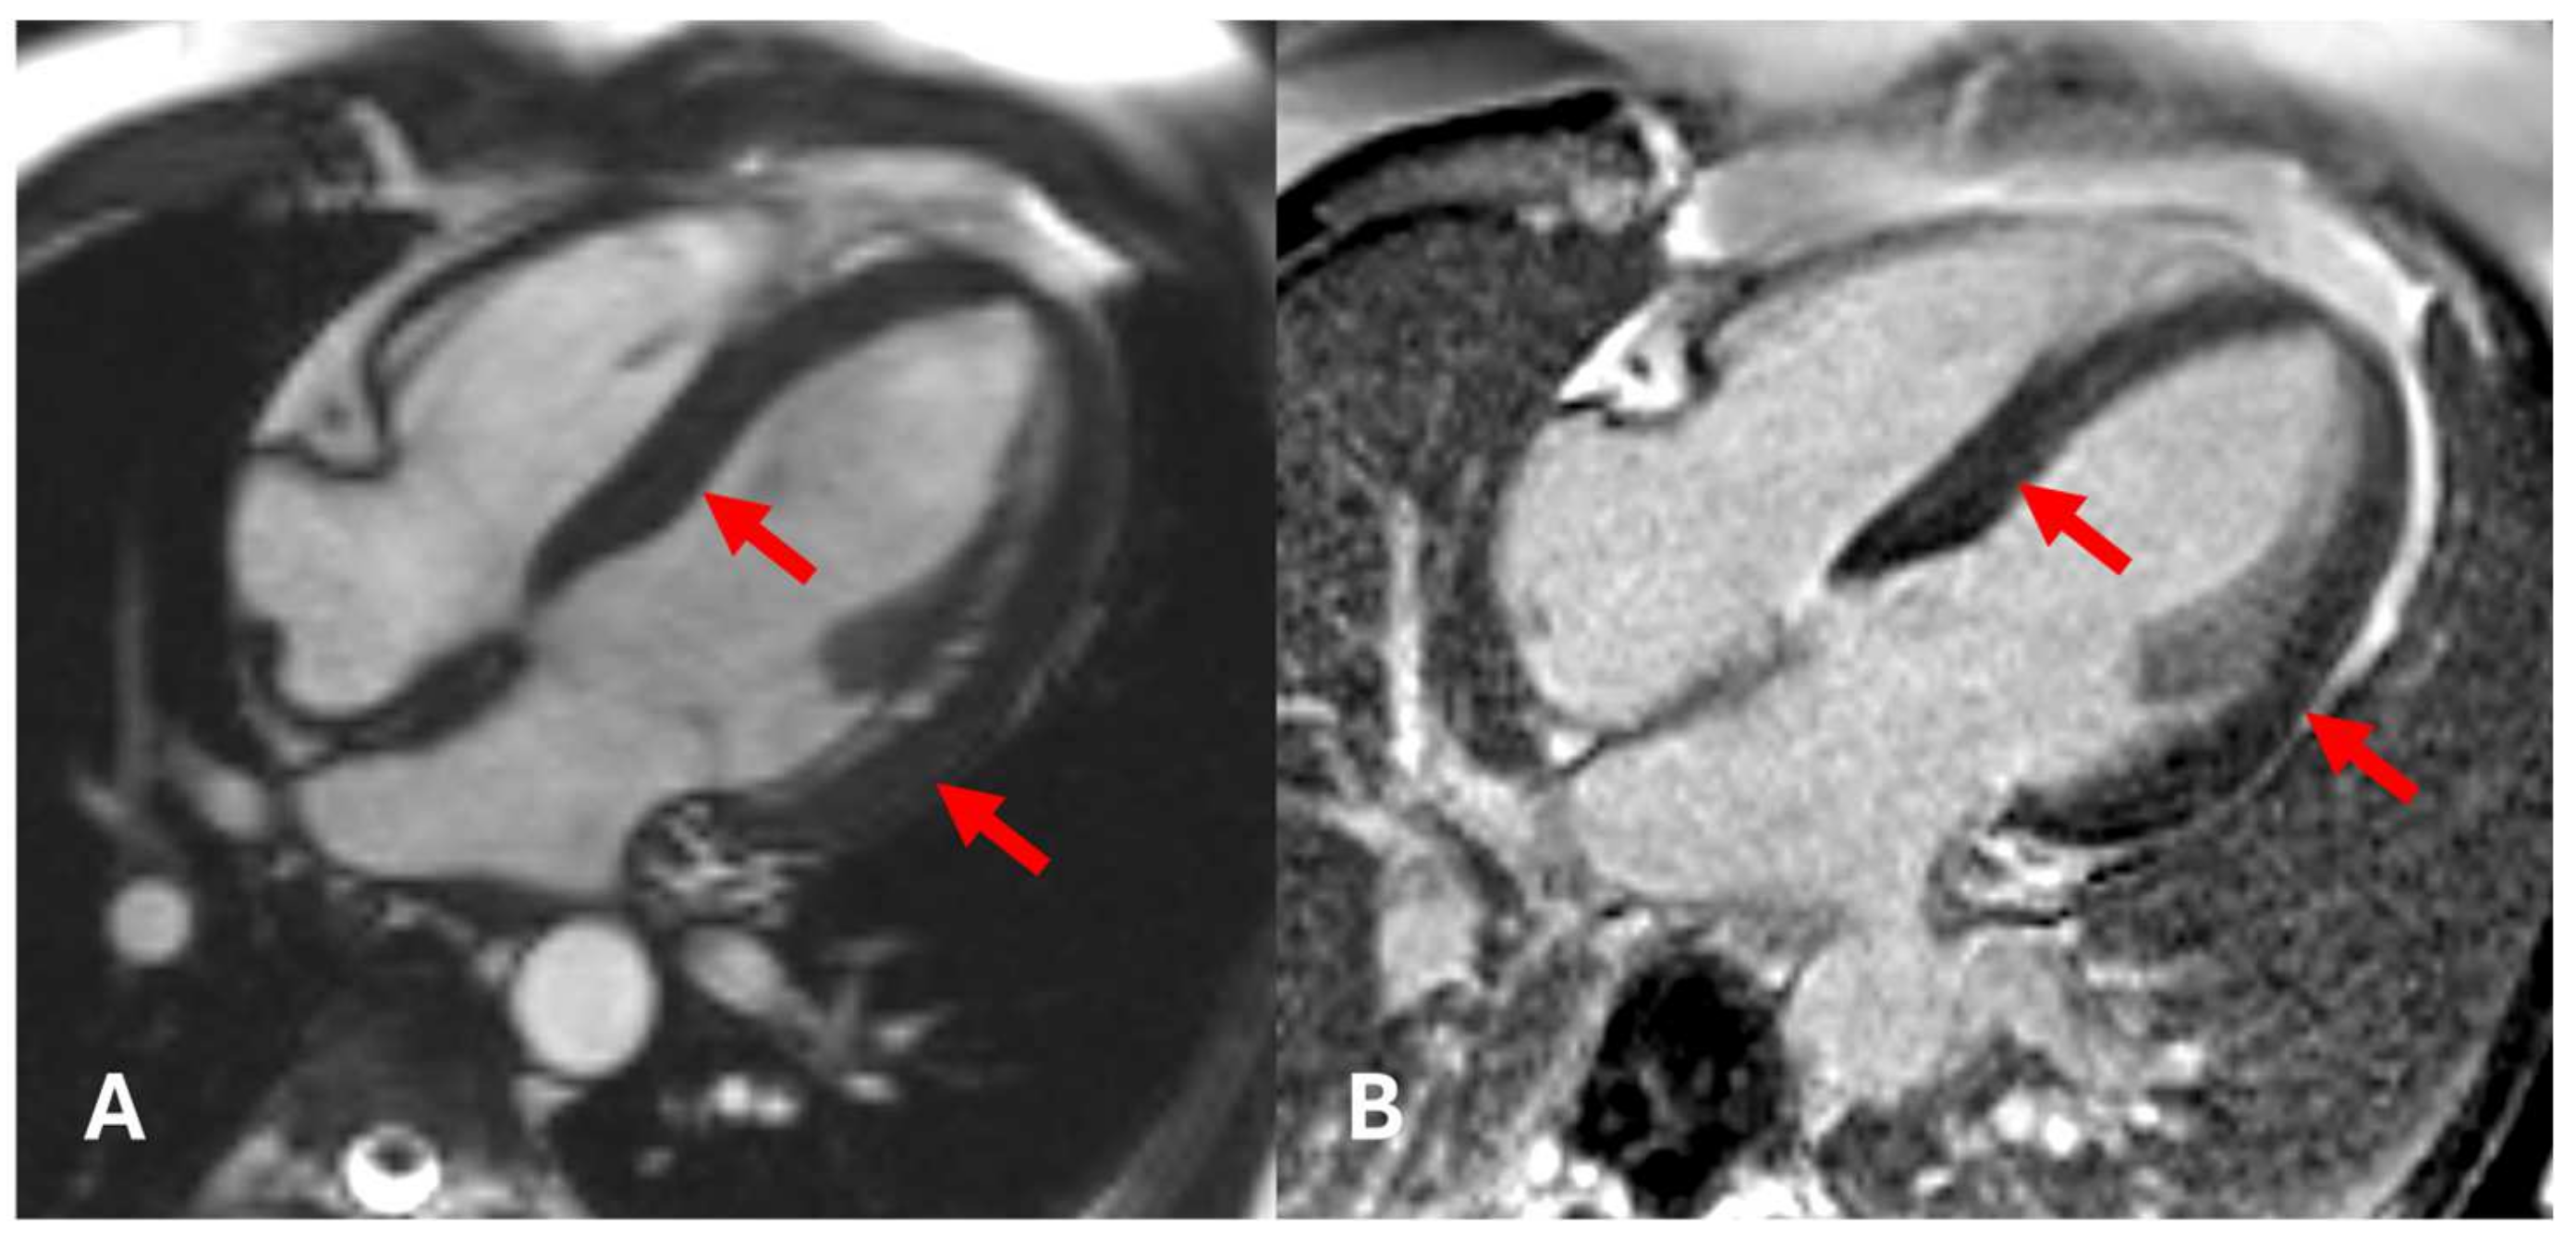

2. Case Presentation